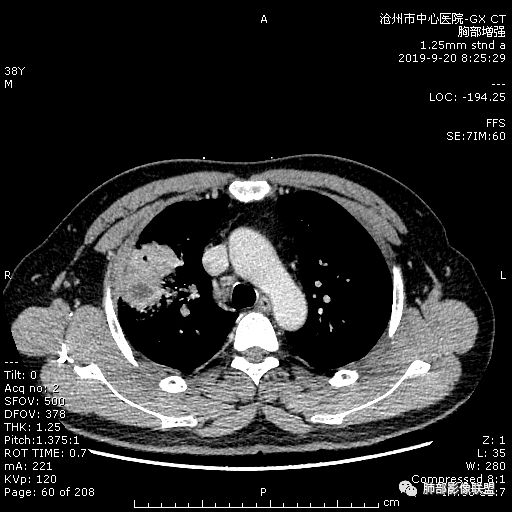

青年男性,肿瘤指标无异,右上中肺团片影,形态不规,跨叶生长,

病灶内见坏死,增强边缘强化,考虑炎性肉芽肿,TB,鉴别鳞。

年轻男性,咳嗽2月,痰中带血,胸痛,炎症指标稍高,肿标正常。影像,右肺上叶不规则团块影,浅分叶,伴边界不清磨玻璃影,从外周向内分布,局部胸膜增厚,病灶中央坏死,坏死边界尚清,空洞形成,空洞内壁光滑;考虑炎性肉芽肿性病变,结核可能,鉴别恶性肿瘤及真菌感染。病灶分布特点不考虑隐球。

右肺上叶不规则病灶,密度不均,有分叶,边缘不清,中央有坏死,坏死壁尚光滑,增强壁有强化,病灶有外朝内,整体收缩为主,慢性病程,考虑炎性病变,肺脓肿或者结核,淋巴结肿大,支气管截断,胸膜脂肪间隙变窄,加个鉴别恶性肿瘤。

38岁,男性,慢性咳嗽2月,右胸痛8天,无发热;白细胞高,肿瘤标志物不高;右上肺不规则块状影,周围有磨玻璃影,边界清,整体有膨胀感,分叶,与胸膜糊墙,并见栽赃,增强肿块中央坏死,周边强化。综合考虑,考虑恶性,鳞癌可能。

38岁,男性,慢性咳嗽2月,右胸痛8天,无发热。白细胞高,肿瘤标志物不高。右上肺不规则块状影,周围有磨玻璃影,边界模糊,整体有膨胀感,分叶,与胸膜糊墙,可疑栽赃,增强肿块中央坏死,边界清,周边强化明显,强化区有低密度影,壁不规则,跨叶生长,支气管截断,伴支气管扩张,综合考虑腺癌

中年男性,咳嗽2月,伴胸痛8天,少许痰血,无发热中性粒明显增高,低氧,肿标不高,右肺上叶不规则实性肿块,深分叶,局部凹陷呈月牙铲改变,多坏死,多空泡,前段支气管分支似见堵塞,2R、4R、10R和7区淋巴结肿大。考虑肺癌可能,建议支气管镜活检

良孑: 晨读病例,右上肺不规则实变,边界模糊,内可见多发坏死灶,腔内坏死壁厚薄不均,有支气管截断,强化时病灶内血管受累,右肺门淋巴结肿大,从影像上看恶性鳞癌征象较多,但病变明显强化,且坏死壁是均匀强化,炎性标志物高,患者年龄较轻,病史较长,病灶内多个坏死液化灶且内缘光整,综和判断,首先考虑亚急性肺脓肿,其次考虑鳞癌

病灶垮叶,强化明显,病灶内见坏死、空泡,周围模糊,考虑放线菌病?鉴别鳞癌

青年男性,右肺上叶肿块,分叶,明显膨隆,内见空洞与支气管相通,增强环形强化,中心液化坏死。实验室鳞癌指标不高。考虑:1,结核,2,肺脓肿。鉴别鳞癌。

中年男性,咳嗽2月病史伴胸疼。白细胞及中性粒细胞高。右上肺团块影,边缘平直内收,与胸膜宽基底相连,胸膜肥厚,肿块内多灶性坏死,有空泡征,支气管进入,走行自然,近端有阻塞,考虑感染性疾病,肺脓肿。但是有深分叶,鳞癌合并感染也不排除。

右肺上叶不规则病灶,密度不均,有分叶,边缘不清,中央有坏死,坏死壁尚光滑,增强壁有强化,考虑肺脓肿或者结核,但是淋巴结肿大,支气管截断,不除外肿瘤。

3.ct表现:肺脓肿可呈结节状或团块状,有时呈不规则形,气道来源肺脓肿常单发,血行来源常多发,边缘模糊,部分病灶周围可见片状肺实变及磨玻璃影;病灶中央为液化坏死区,若脓肿与支气管相通,脓液排出可形成空洞,空洞内可形成液平;急性肺脓肿内壁多不规则;慢性肺脓肿洞壁较厚,一般不规则或形成多房空洞:CT增强扫描空洞壁可见强化,空洞壁为纤维肉芽组织,呈典型的环形强化;慢性肺脓肿周围可有较广泛的纤维索条影,可伴支气管扩张.肺

气肿或胸膜增厚表现。

今天病例坏死周围也可以看到明显强化的脓肿壁,只是局部脓肿壁不规则模糊,部分脓肿壁规则清楚。